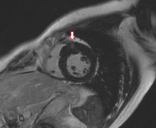

(箭头所指右心室上插入部及前间隔壁增厚的心肌中层存在延迟强化影,提示心肌纤维化)